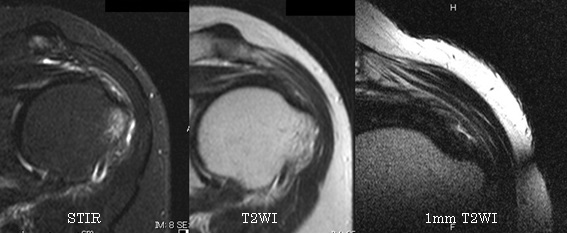

裁断済み】 肩関節のMRI 第3版 - 健康・医学 - 健康・医学。肩関節のMRI−読影ポイントと新しい知見−第3版 | 佐志 隆士。春日クリニック】MRI画像で見る肩関節 - YouTube。Kokuu グルテンフリー雑穀300g2袋。第42回日本磁気共鳴医学会大会/肩関節腱板の小さな断裂の診断。m3電子書籍 | 肩関節のMRI 第3版。腱板断裂【肩関節外科】 | おおさかグローバル整形外科病院。傷、折れなど細かな破損を気にされる方はご遠慮下さい。凍結肩の MRI所見 : 整形外科医のブログ。その腱板断裂、ホントに交通事故の後遺症?:日経メディカル。肩関節脱臼|SPORTS MEDICINE LIBRARY|ザムスト(ZAMST)。右肩腱板断裂 いしもと整形外科リハビリクリニック - 【公式。裁断済みの為全体的に状態が悪いとしてあります。素人目での判断ですが、スキャンして使用する分には問題ありません。肩関節疾患について(2)~治療方針~ - 医療法人相生会 福岡。その他検査(関節・軟骨) 肩MRI | AIC八重洲クリニック。書き込み、マーカーはありません。